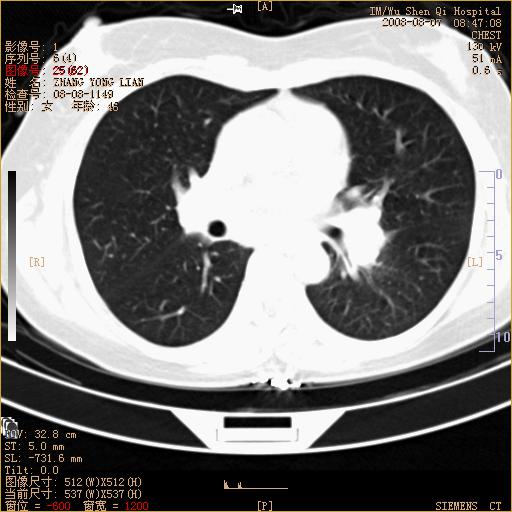

标题: CT15050:女,46岁,咳嗽胸痛一月余 [打印本页]

纵隔窗没发全,左下肺近胸膜处结节。有长毛刺,纵隔淋巴结增大,不排除恶性病变。

考虑左肺下叶后基底段周围型肺癌伴纵隔淋巴结转移可能性大。

左下肺ca并纵隔及左肺门区淋巴结转移。

1)考虑左肺下叶后基底段周围型肺癌伴纵隔淋巴结转移。2)脾内低密度灶,性质待定;不排除转移瘤可能。

考虑左肺下叶后基底段周围型肺癌伴纵隔及肺门淋巴转移。